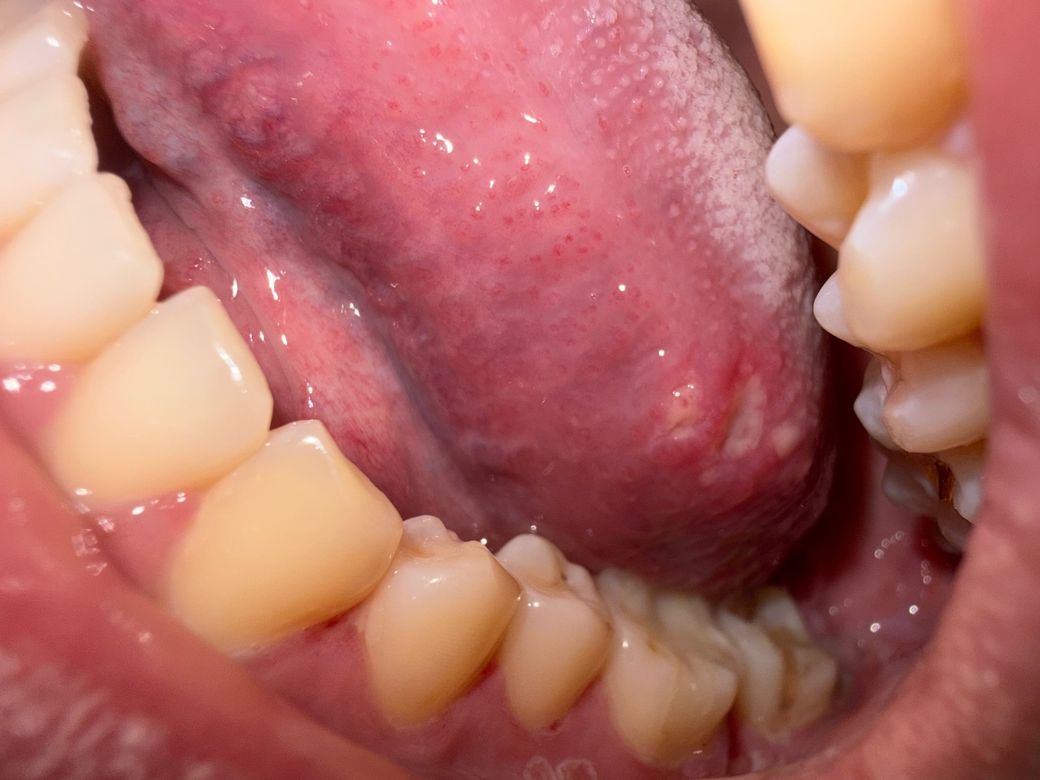

그리고 혀에 저 하얀건 구내염이 맞나요?

혀 측면의 하얀 병변은 중심부가 희고 주변이 붉은 형태로, 아프타성 구내염 양상과 유사합니다.